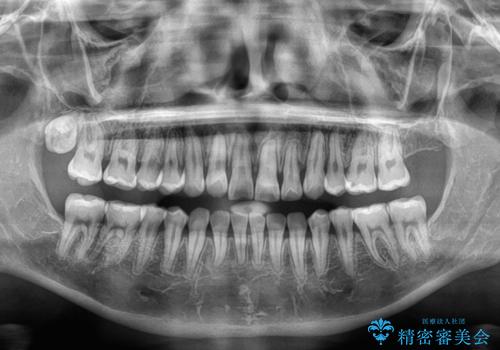

- 1年8ヶ月

- 左上の前歯のがたつきを主訴に来院された患者様です。

上顎歯列が下顎の歯列に対して狭小であり、一部下顎の奥歯が上顎よりも外側に位置している状態でした。

上顎の歯列を拡大しスペースを設け、さらに左上の小臼歯を一本抜歯し左上の八重歯を歯列内に入れ整えていくことにしました。